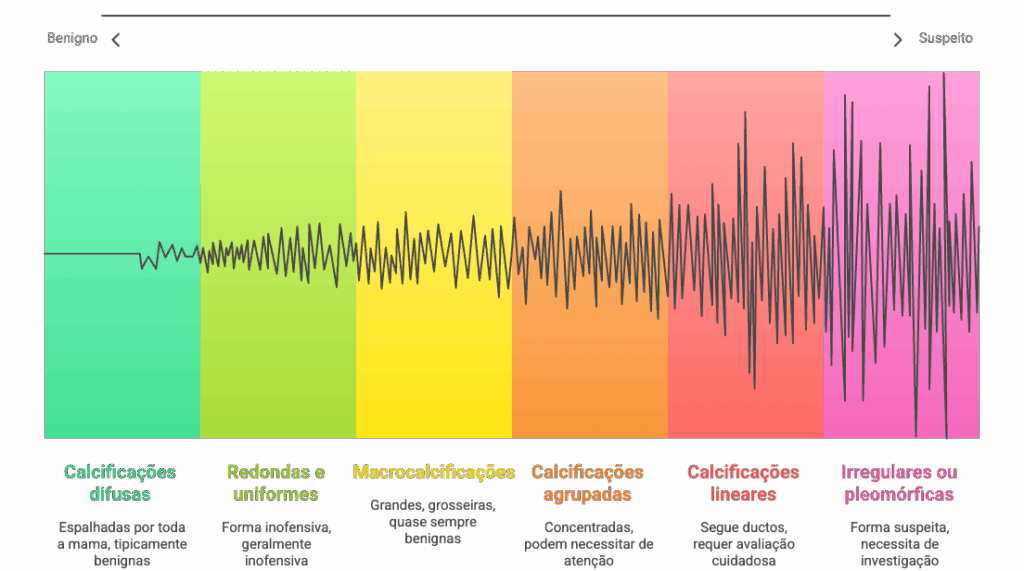

Quando analisamos uma mamografia, não olhamos apenas se há calcificações, mas sim suas características. Elas nos contam uma história sobre o que está acontecendo na mama.

1 – Padrão e Distribuição

- Calcificações difusas: Espalhadas por toda a mama, geralmente benignas

- Calcificações agrupadas: Concentradas em uma área específica, podem necessitar maior atenção

- Calcificações lineares: Seguem ductos mamários, requerem avaliação cuidadosa

2 – Forma

- Redondas e uniformes: Geralmente inofensivas

- Irregulares ou pleomórficas: Podem ser suspeitas e necessitar investigação

3 – Tamanho

Macrocalcificações:

- São maiores, grosseiras, com contornos bem definidos e geralmente dispersas pela mama;

- Quase sempre (em mais de 99% dos casos) estão associadas a condições benignas, como envelhecimento dos tecidos, artérias da mama, cistos antigos ou fibroadenomas (nódulos benignos) em degeneração.

Microcalcificações:

- São pontinhos muito pequenos, finos e que frequentemente aparecem agrupados em uma área específica da mama.

- Este é o grupo que exige mais atenção, pois, dependendo de suas características, pode indicar a presença de células com atividade aumentada.